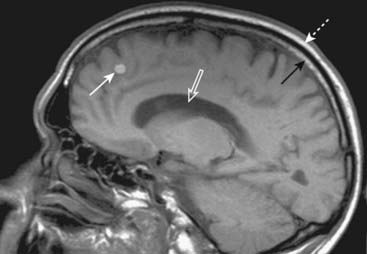

Figure 20-5 Metastatic melanoma.

Sagittal T1-weighted image of the brain demonstrates a bright mass (solid white arrow) in the frontal lobe representing metastatic melanoma. Notice that both the yellow bone marrow within the skull (solid black arrow) and the overlying subcutaneous fat (dotted white arrow) are bright. We can tell that this is a T1-weighted image because the CSF in the lateral ventricles is dark (open white arrow).